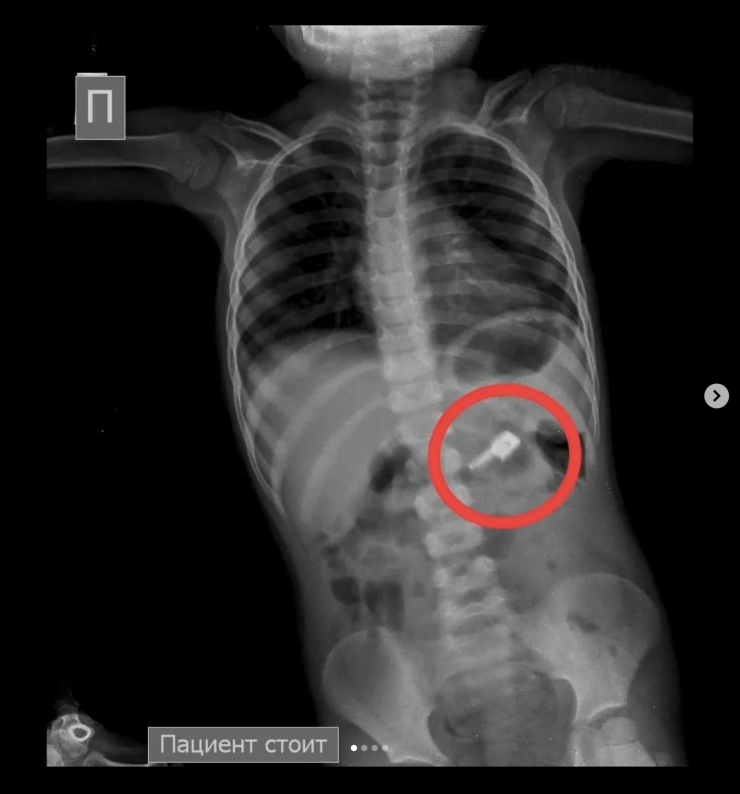

"На обзорной рентгенограмме брюшной полости был обнаружен бегунок и, предположительно, две швейные иглы в проекции желудка. При проведении процедуры ЭФГДС из желудка удалена одна игла, бегунок отсутствовал. Пациент был оставлен в хирургическом отделении Жамбылской областной многопрофильной детской больницы под наблюдением специалистов", - рассказали врачи детской больницы.

В результате бегунок со стулом вышел самостоятельно. В то же время другая игла не выходила.